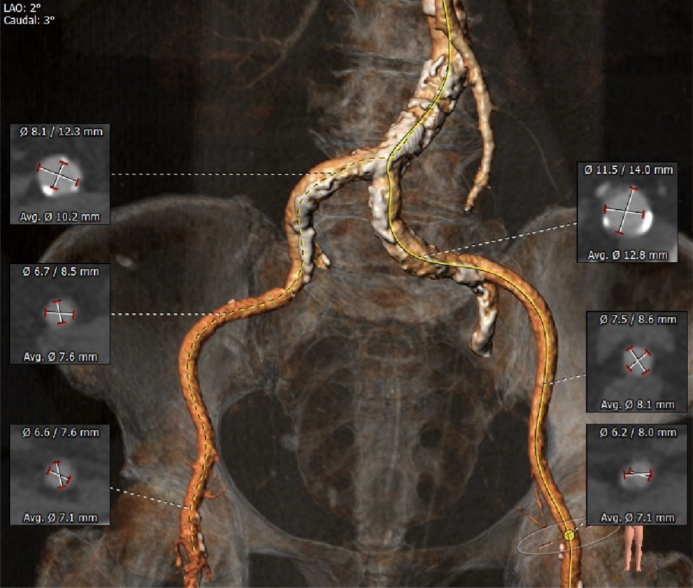

CT数据显示该患者为三叶三窦式主动脉瓣。

主动脉瓣瓣环周长77.0mm,平均周长径 24.5mm;LVOT周长89.1mm,平均周长径28.4mm;SOV:28.5mm*29.3mm*32.0mm;STJ平面周长94.6mm;瓣叶增厚,瓣上钙化明显,HU850积分1341mm³, HU560积分2499mm³,升主动脉最大直径44.1mm。

左冠开口高度11.0mm,右冠开口高度15.0mm,左冠高度较低,根据瓦氏窦内径和瓣叶长度综合判断,左冠堵塞风险不高;右冠瓣叶长度较长,存在一定封堵风险,合并患者原有冠脉疾病,考虑右冠灌注不良风险较高;左室腔增大,心室壁未见明显增厚。

入路血管严重钙化并有较大迂曲,双侧血管内径良好,主动脉弓部见环状钙化。